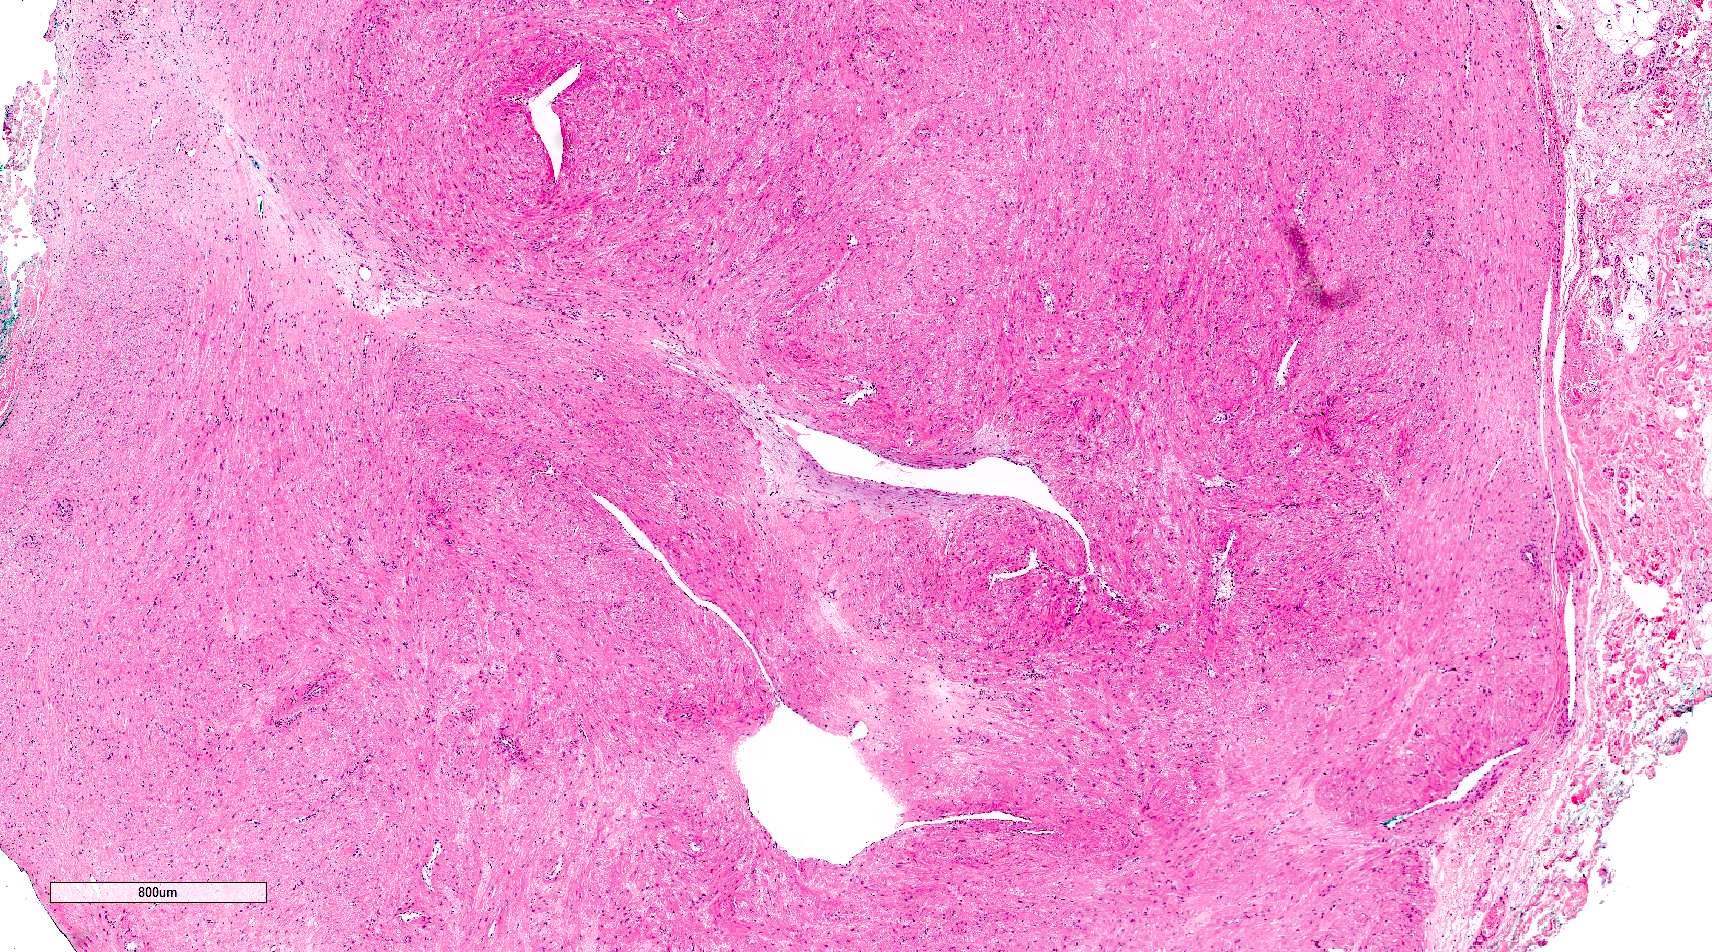

Microscopic (histologic) description

- Encapsulated proliferation of eosinophilic smooth muscle cells with minimal nuclear pleomorphism

- Rounded or slit-like veins with muscular walls present within the tumor (J Cutan Pathol 2017;44:342)

- Tumors can further be classified into 3 subcategories, first described by Morimoto et al:

- Solid type: smooth muscle bundles surround numerous small slit-like channels

- Venous type: thick walled vessels that are easily distinguished from the intervascular smooth muscle

Microscopic (histologic) images

Contributed by Ohoud Aljarbou, M.D., Jijgee Munkhdelger, M.D., Ph.D. and Andrey Bychkov, M.D., Ph.D.

A. Angioleiomyoma. A mixture of smooth muscle bundles arranged in small fascicles and intervening vascular channels is noted. The concentric perivascular spindle cell proliferation which is characteristic for myopericytoma is absent. There are no glomus cells seen. Adipocytes are not seen in this image, which makes angiomyolipoma less likely.